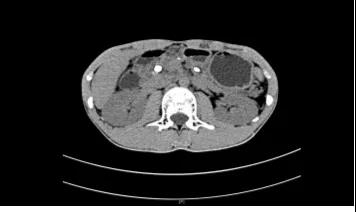

查了腹部CT,

结果提示:

胰管多发结石,

伴胰管不均匀扩张,

胰腺实质萎缩,

并被收治入院。

经过详细的术前检查,医生发现小黄整个胰管充满结石,尤其是胰头部及胰尾部主胰管和分支胰管均有大量结石,胰体部主胰管有结石而分支胰管结石少。

(术前CT图)